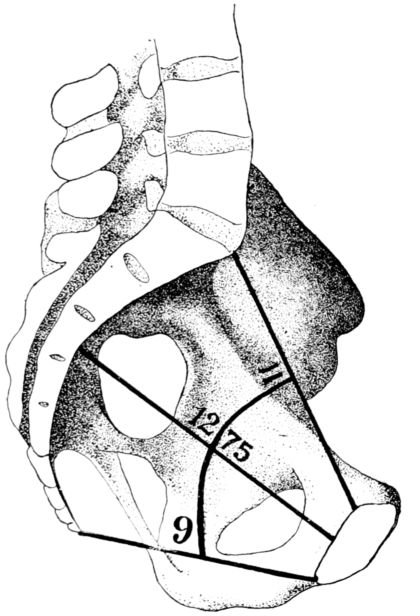

25In considering the question of pelvimetry, we find that there are both external and internal measurements to be taken, all for the purpose of estimating as accurately as possible the shortest diameter of the inlet through which the baby must pass. (Fig. 5.)

According to a common system of mensuration, the first external measurement is the inter-spinous, the distance between the anterior-superior spines, those bony points which are uppermost as the patient lies on her back. This distance is normally 26 centimetres. (Fig. 6.)

The second measurement is the inter-crestal, or the distance between the iliac crests, and is normally 28 centimetres.

Baudelocque’s diameter is the third measurement and is taken with the patient lying on her side. (Fig. 7.) It is the distance from the top of the symphysis to a depression just below the last lumbar vertebra. This depression is easily located as it also marks the upper angle of a space just above the buttocks, which in normal pelves is quadrilateral. In malformed pelves this quadrangle may be so misshapen as to become almost a triangle with the apex directed either up or down. This dimension 26is sometimes called the external conjugate and ordinarily measures 21 centimetres.

The fourth measurement is the distance between the great trochanters, or heads of the femora, and normally is 32 centimetres.

All of these measurements, which after all are only approximate, relate to the top of the pelvis and are valuable in that they help in estimating the dimensions of the inlet, which are the important ones, and obviously cannot be measured on a live woman.

Fig. 6.—Diagram showing method of measuring distances between iliac crests and spines and the trochanters.

The inlet has four measurements of obstetrical importance: the antero-posterior, or true conjugate, which is the distance from the top of the symphysis pubis to the prominence of the sacrum, and is normally 11 centimetres; the transverse diameter, which is at right angles to the true conjugate and is the greatest width of the inlet, measuring from a point on one side of the brim to the corresponding point on the other, is normally 13.5 centimetres, and the two diagonal measurements, known respectively 27as the right and left oblique diameters, which are normally 12.75 centimetres.

The length of the all important, true conjugate is estimated by introducing the first two fingers of one hand into the vagina until the tip of the second finger touches the promontory of the sacrum. (Fig. 8.) The point at which the inner margin of the symphysis then rests upon the forefinger is measured, thus giving the length of the diagonal conjugate. This normally measures 12.5 centimetres or more, and is estimated as being 1.5 centimetres longer than the true conjugate.

28The most important measurement of the outlet is the intertuberous diameter, the distance between the tuberosities of the ischii. This is the shortest diameter through which the child must pass in the inferior strait, and normally measures something more than 8 centimetres, usually about 11 centimetres. (Fig. 9.)